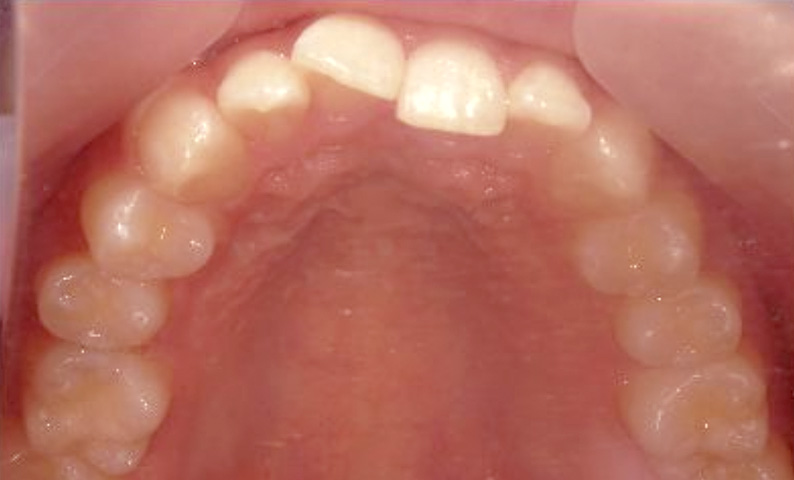

症例_004 上顎だけの部分矯正

治療期間:6ヶ月金額:27万円+税男性出っ歯上の前歯だけ

| Before | After |